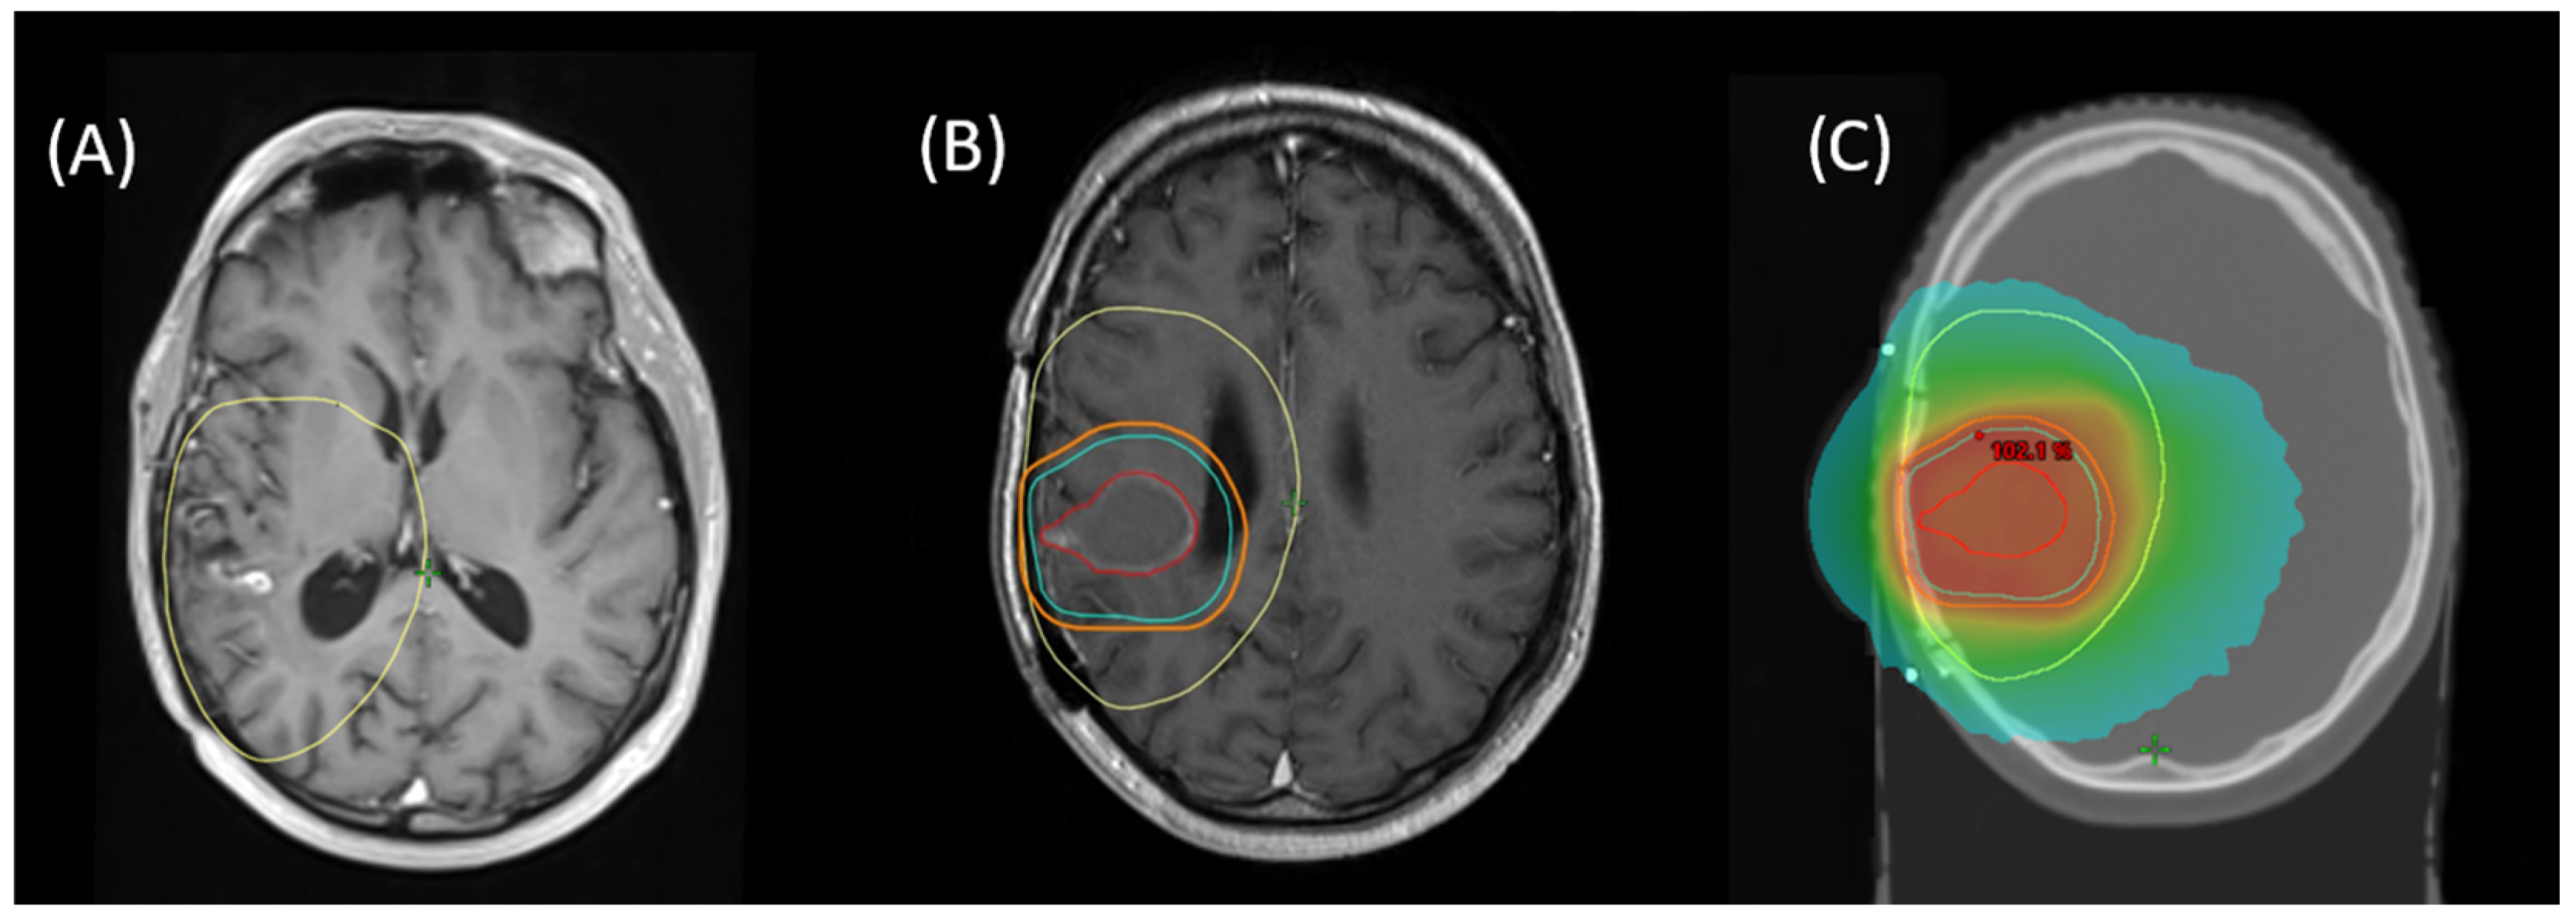

- Chemoradiotherapy